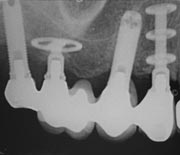

Basal implants are one of the newest implant systems in India which are also known as immediate loading implants. These implants (along with the prosthesis) can be placed in a matter of three days which is a great plus point for patients.[caption id="attachment_2793" align="alignleft" width="180"]

Basal implants[/caption]Basal implants are placed in the basal bone, which is dense in nature. It is less prone to infection and resorption, provides better support.In case of any bone deformities, an implant requires pre-prosthetic surgery in order to get embedded into the bone. But in the case of basal implants, the need for such surgery is eliminated.While placing the basal implant one need not worry much about the systemic conditions they if they have any. They can be placed in patients with cardiovascular disorders, immunosuppression, and cancer patients too. This is because of minimal invasion and fast healing.

The only disadvantage of the basal implant is the compromised aesthetics in a few patients.